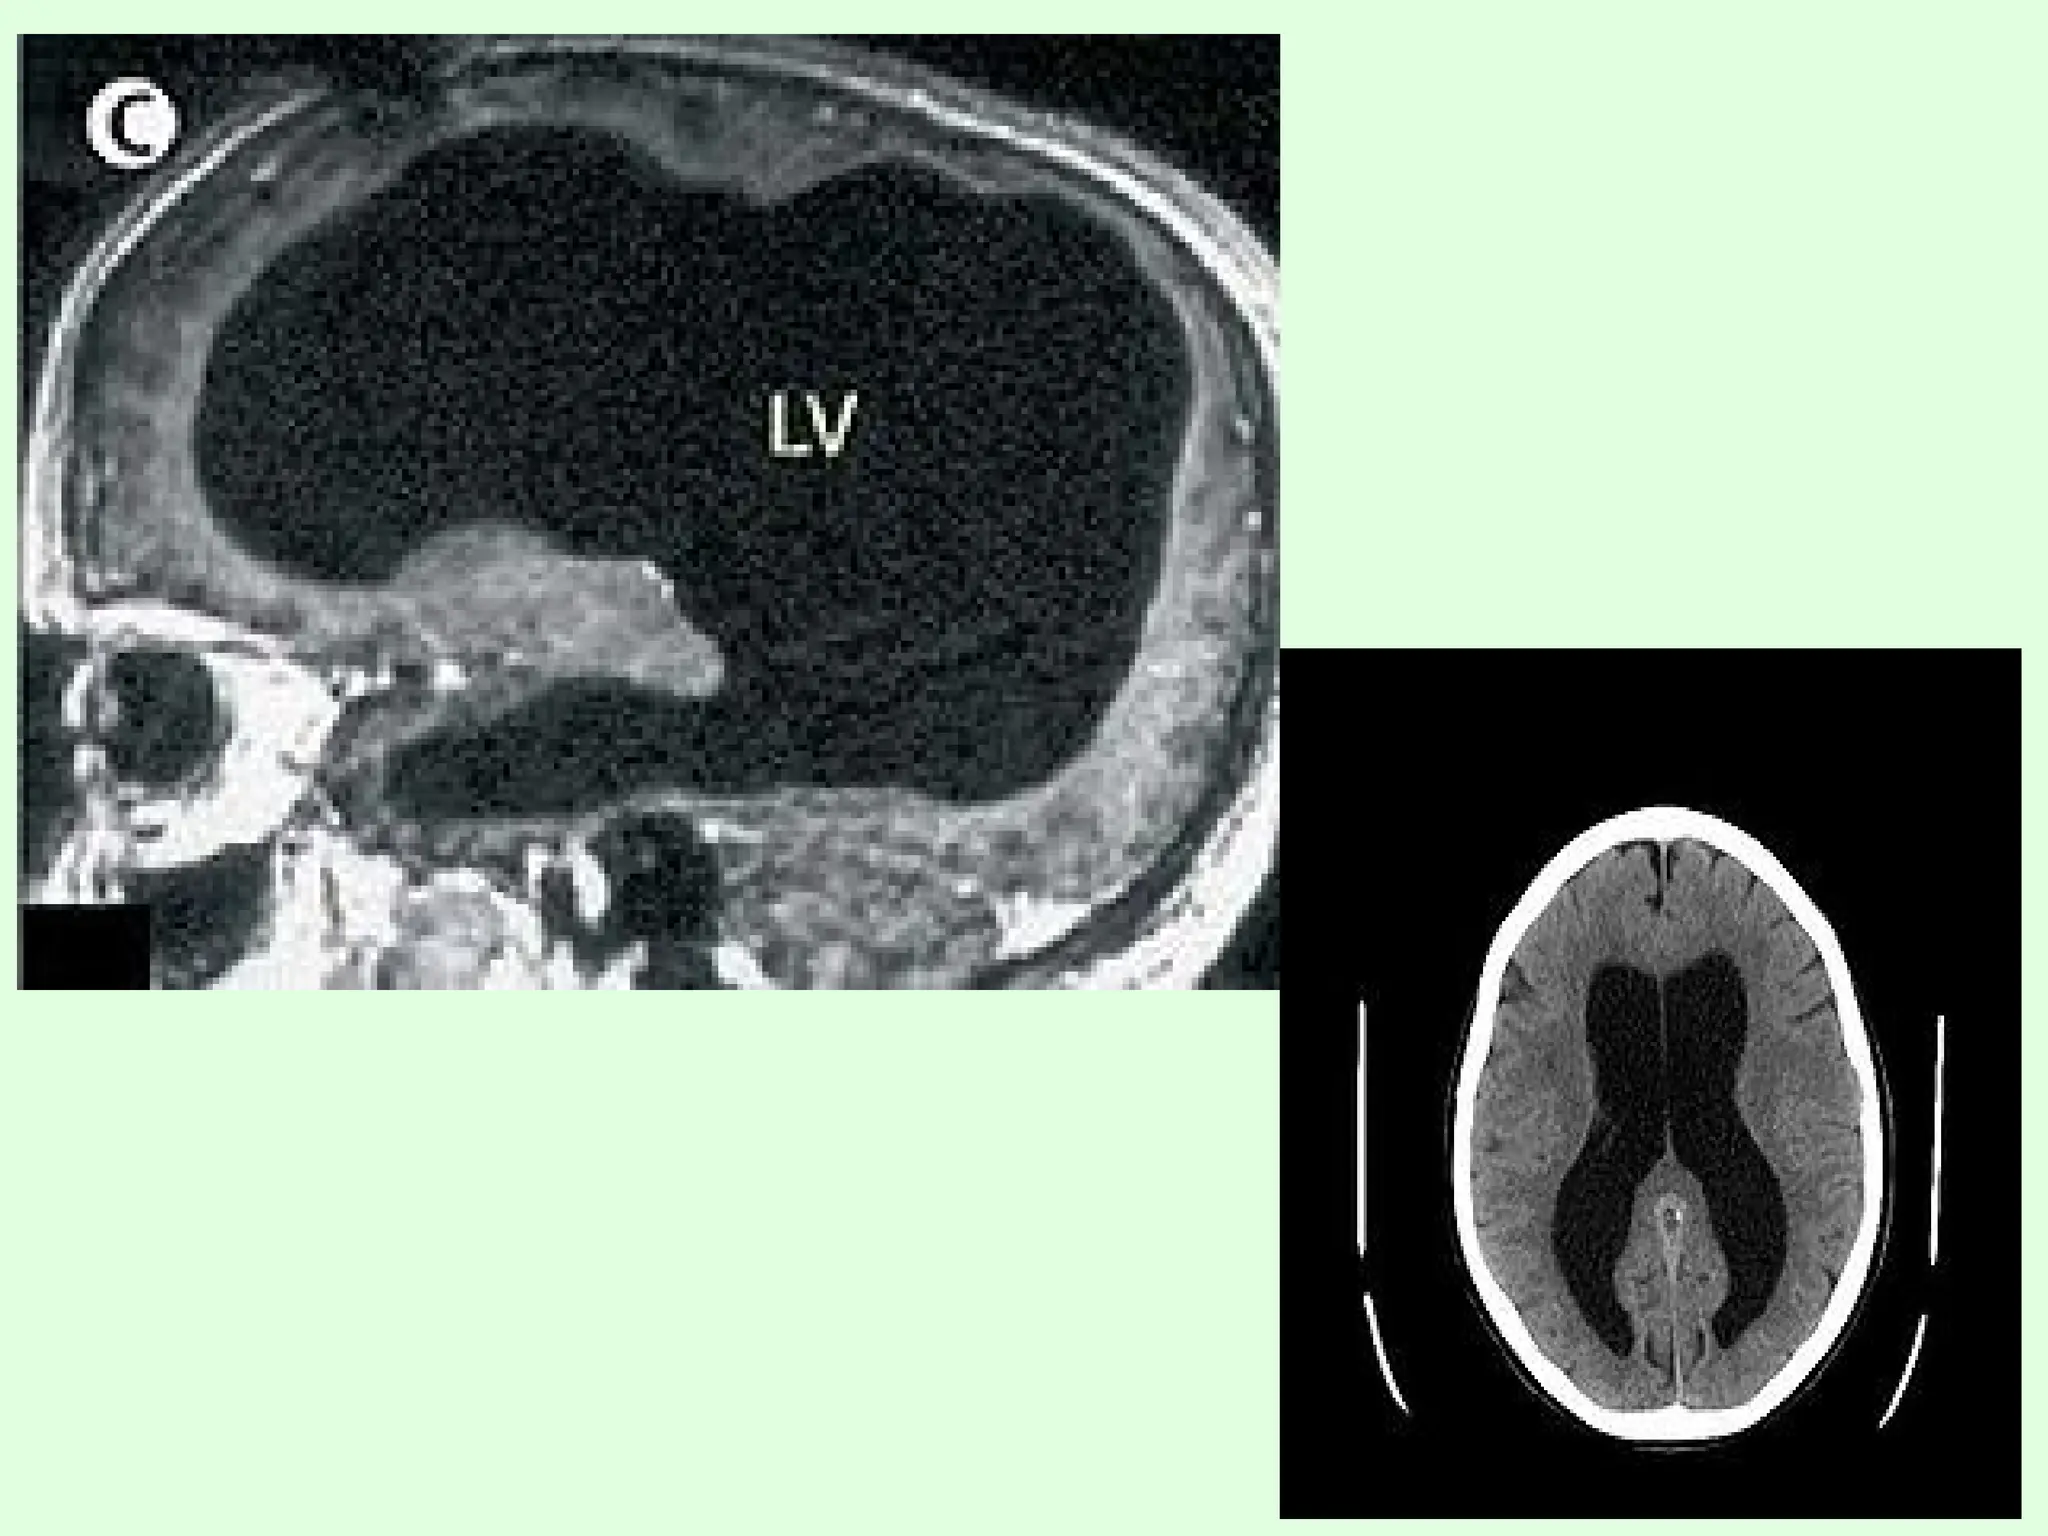

3) IMAGING STUDIES:

b) CT Scan and MRI

 Ventricular size can be assessed more accurately with CT scan.

 Information about cortical mantle, periventricular ooze and etiology

of hydrocephalus like Arnold chiari and dandy walker malformation

 In children CT shows COPPER BEATING of skull because of chronic

raised ICP.

 MRI/CT may be necessary to determine site of obstruction and in

congenital hydrocephalus to identify associated malformation.

 MRI provide better anatomical detail of lesion and is particularly

helpful in diagnosis of aqueductal stenosis